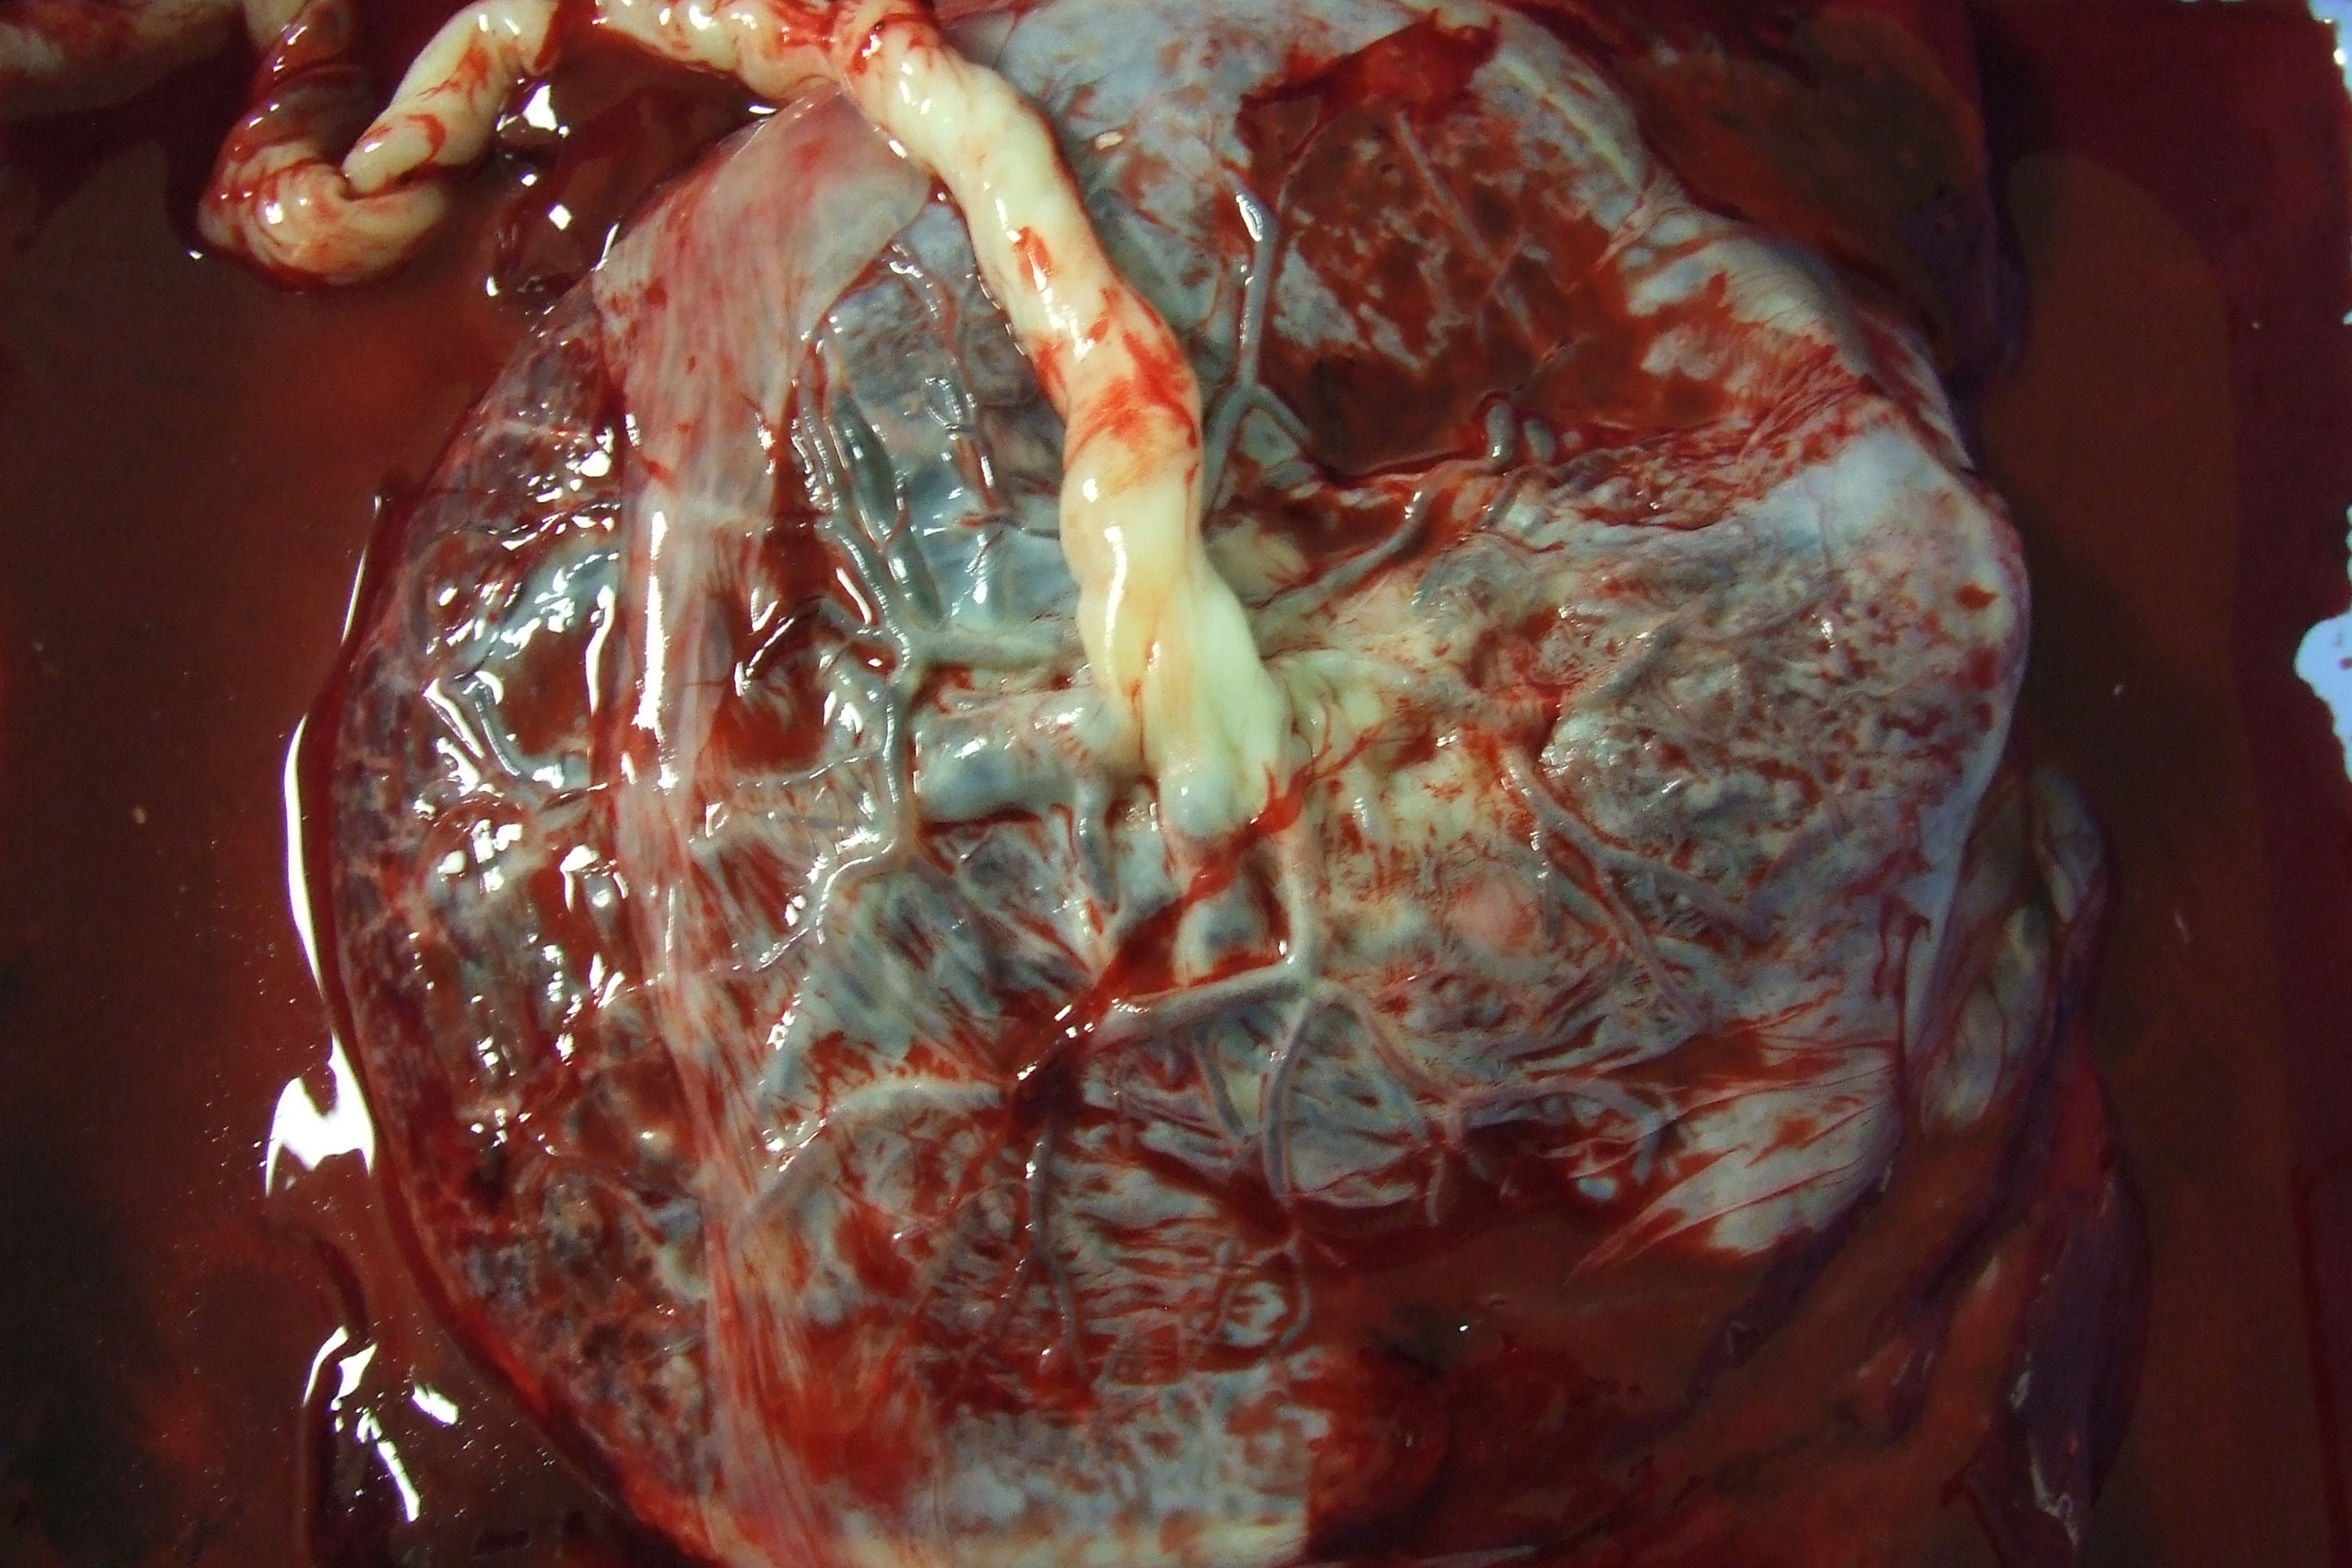

탯줄은 태아와 태반을 연결하는 기관으로, 출생 시 굵기 2cm, 길이 50~60cm 정도이다. 탯줄에는 2개의 제대 동맥과 1개의 제대 정맥이 있으며, 이 혈관 속 혈액이 제대혈이다.[49] 제대혈은 출산 후 태반이나 탯줄에 남아있는 혈액을 채취하여 보존한 것이다.[51][52] 이전에는 폐기되었으나, 1980년대 초반 조혈 줄기 세포가 포함되어 있다는 사실이 밝혀졌다. 1988년에는 제대혈을 사용한 최초의 이식(Fanconi 빈혈 아동 대상)이 이루어졌고,[53] 이후 각국에서 제대혈 은행이 설립되어 백혈병 등 질환 치료에 활용되고 있다.

출산 후 탯줄은 신생아에게서 절단되고 태반도 배출되므로, 탯줄에서 혈액을 채취해도 신생아나 산모에게는 영향이 없다.[54]

제대혈은 아기가 태어난 후 태반과 탯줄에 남아 있는 혈액이다. 제대혈 채취는 일반적으로 "밀폐 기술"을 사용하여 이루어진다.[13] 이 방법은 표준 혈액 채취 기술과 유사하며, 기술자는 혈액 백에 연결된 바늘을 사용하여 절단된 탯줄의 정맥에 캐뉼라를 삽입하고, 제대혈은 바늘을 통해 백으로 흘러 들어간다. 평균적으로 약 75ml의 제대혈을 채취할 수 있다.[14]

출산 후 탯줄은 신생아로부터 절단되고, 태반도 곧 배출(후산)된다. 신생아로부터 절단된 후의 탯줄로부터 혈액을 채취해도 신생아나 모체에는 아무런 영향이 없다.[54]